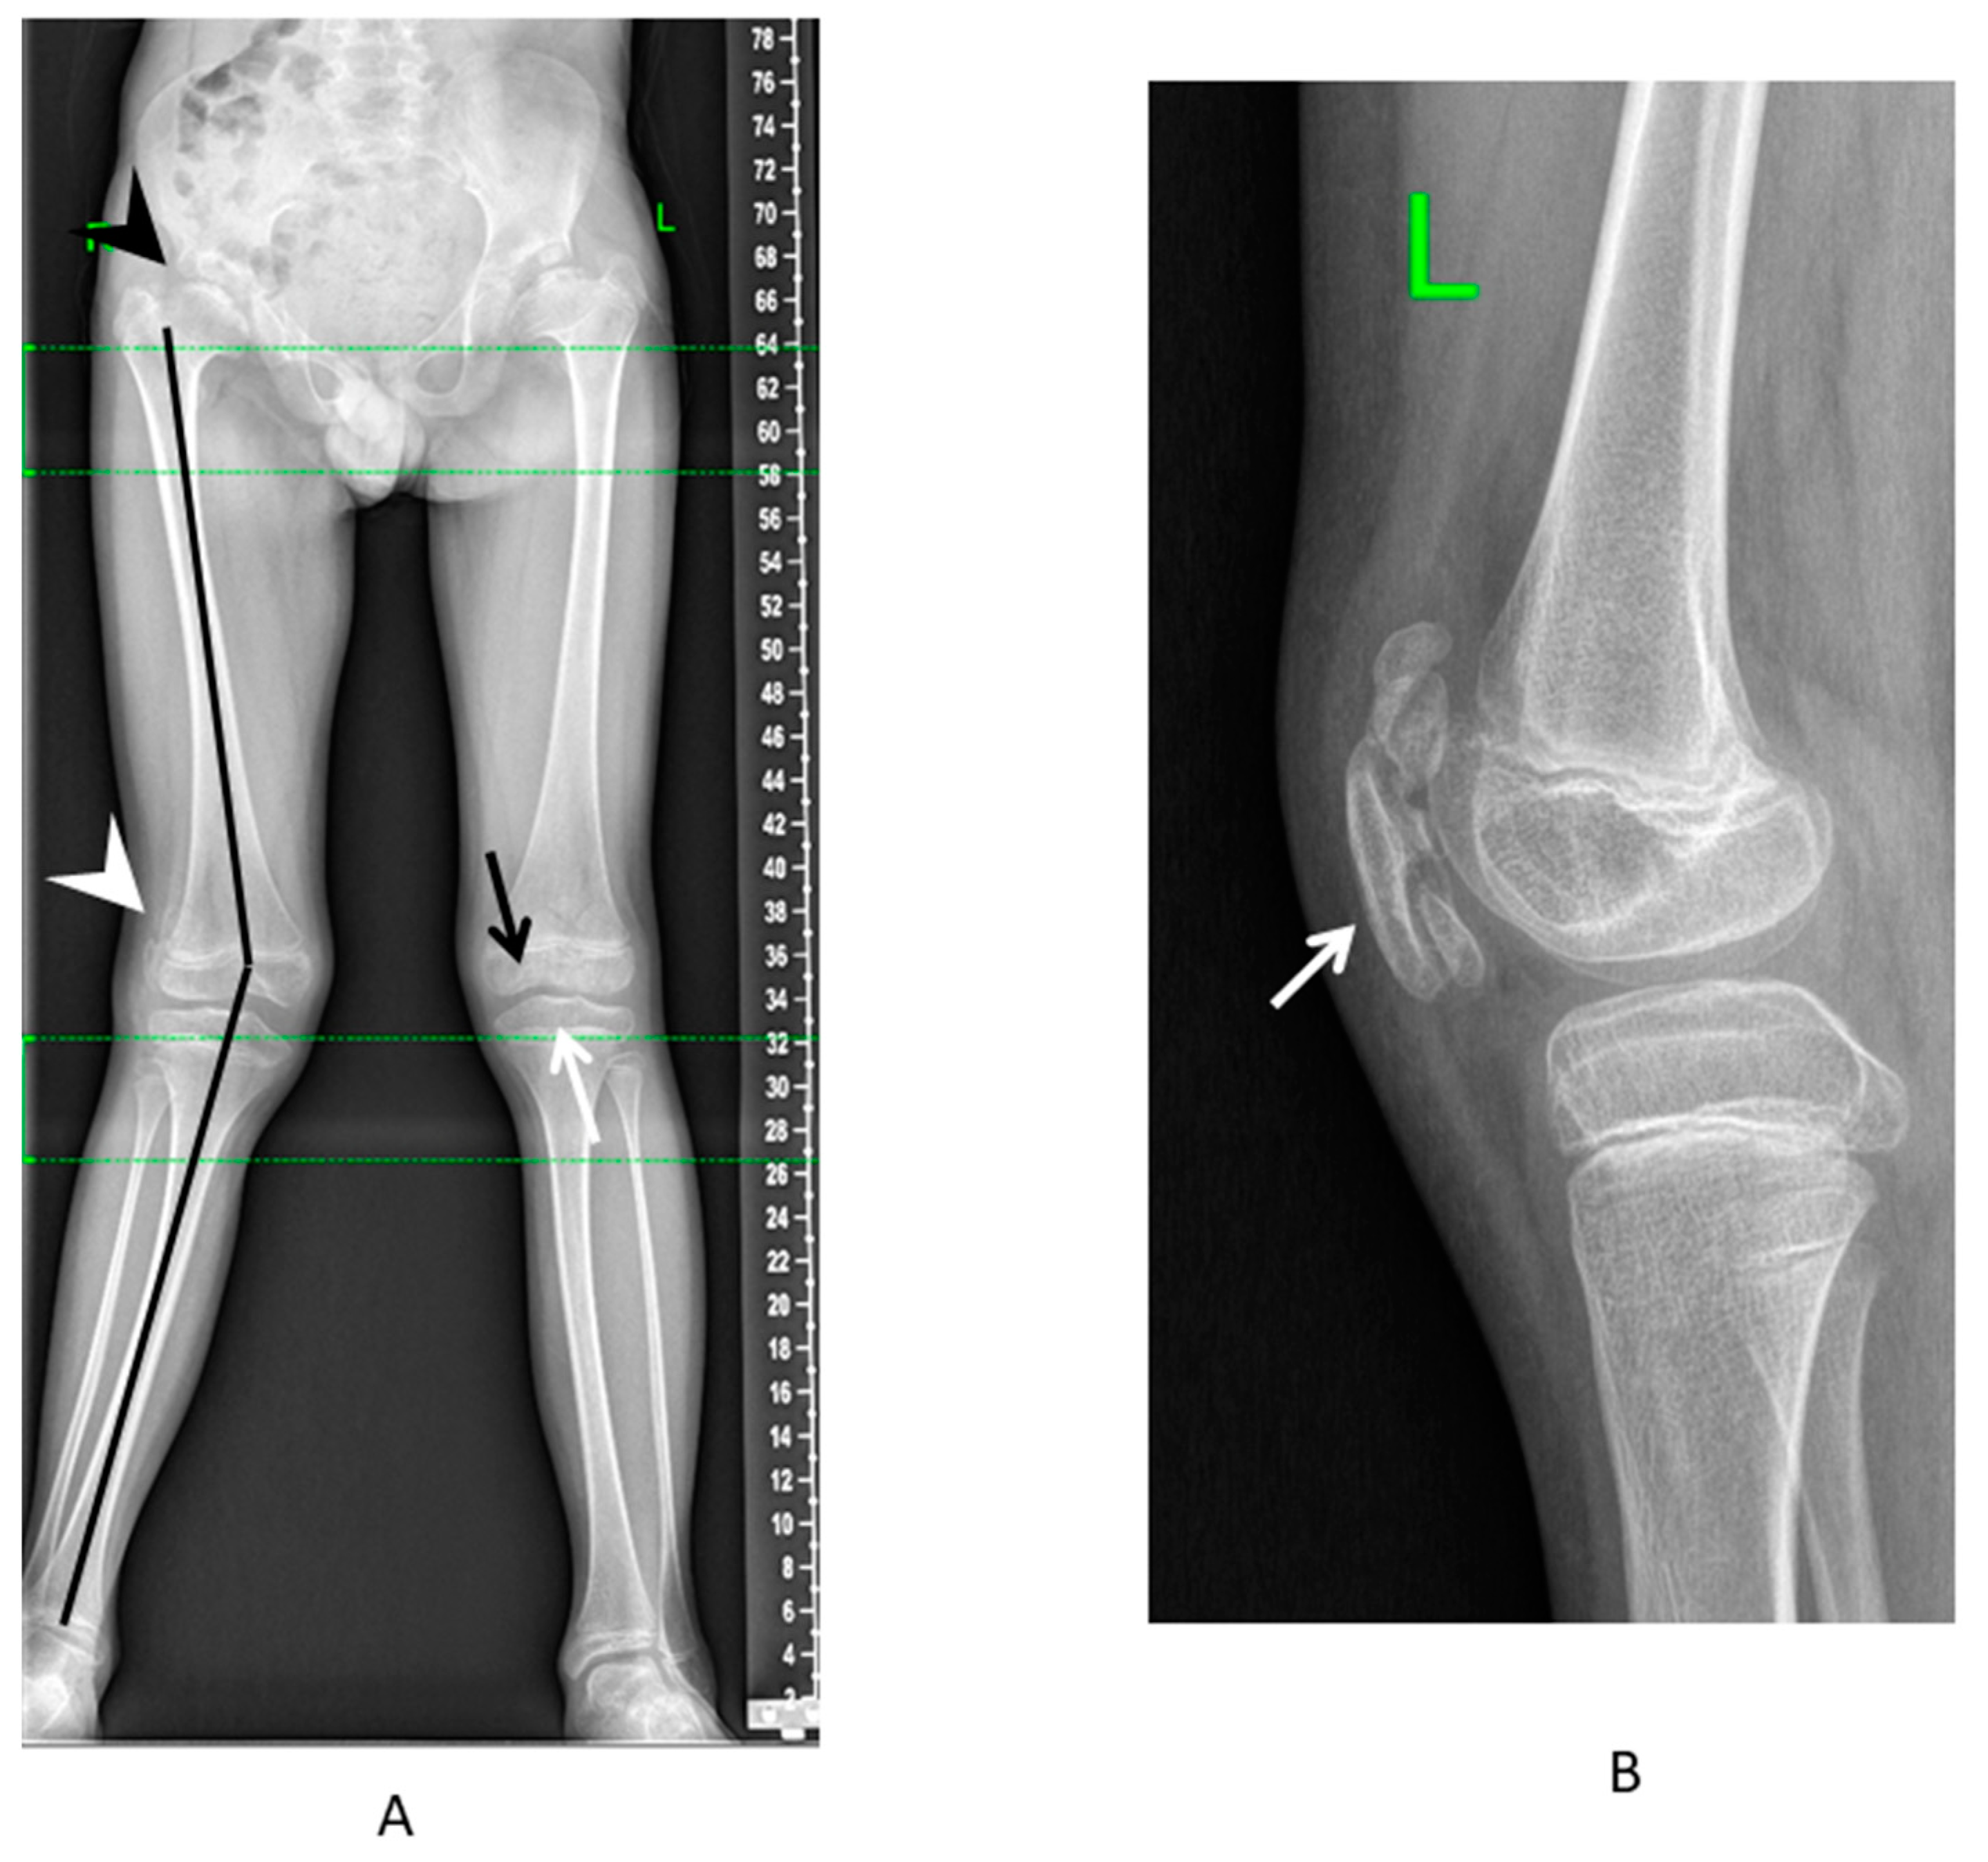

The pathology of the knee joints primarily involved the femoro-patellar joint, which led to the lateral subluxation or habitual dislocation of the patella, usually at the age of 5–7 years (20%) (Figure 3A). Some patients had mild or moderate scoliosis (49%) and lumbar hyperlordosis (54%). The distinctive radiological sign detected in the majority of patients who had lateral knee radiographs available for the analysis (17 out of 18 patients) was the characteristic pattern of ossification—a multilayer structure of the patellar (Figure 3B). The multilayer patella can also be detected earlier (before ossification occurs) using the ultrasound as the “layering” of the US-signal from the patella, as can be seen in the patient with MED type 4 in the first year of life.

Figure 3. Typical lower limb involvement in patients with MED type 4. (A) Standing anteroposterior radiograph of the lower limbs: valgus deformity of the axis (black line), mushroom-shaped deformity of the femoral head (black arrowhead), lateral patellar subluxation (white arrowhead), flattening of the distal femoral (black arrow), and proximal tibial (white arrow) epiphyses. (B) Lateral radiograph of the knee—multilayer patella (white arrow).